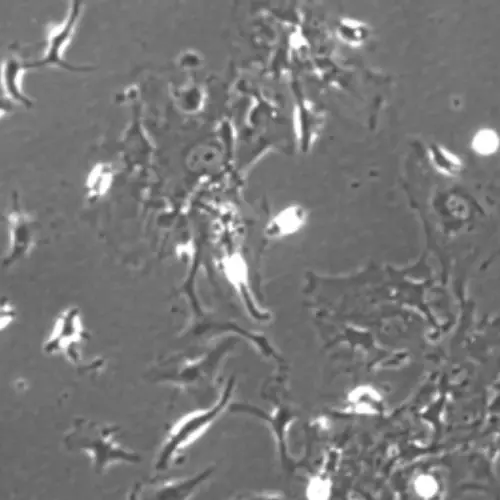

Mouse Derived Mesenchymal Stem Cells

Mesenchymal Stem Cells derived from adipose tissue have immense regenrative potential. They are responsible for replacing damaged tissue and maintaining an extracellular matrix. They are used for toxiticity analyisis and drug development proccesses. They are also used in variety of in vitro assays.